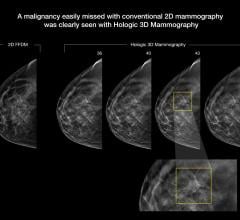

Despite decades of progress in breast imaging, one challenge continues to test even the most skilled radiologists ...

Stamatia Destounis, M.D., FACR, associate professor, University of Rochester School of Medicine, and attending ...